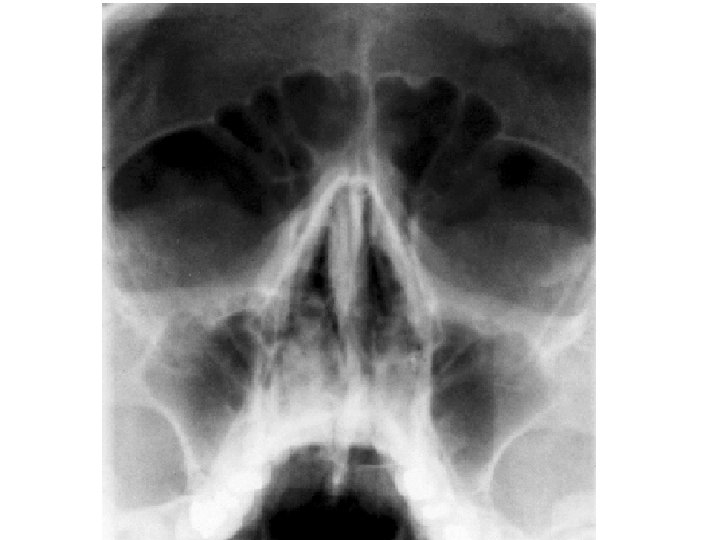

Paranasal Sinuses

Frontal sinus

Ethmoidal sinusitis

Nasal meatus • Sphenoethmoidal recess: sphenoidal sinus • Sup. Meatus: post. Ethmoidal sinuses •

Nasal meatus • Sphenoethmoidal recess: sphenoidal sinus • Sup. Meatus: post. Ethmoidal sinuses • Middle meatus: -Bulla ethmoidalis← middle ethmoidal air sinuses Hiatus semilunaris← maxillary sinus, infundibulum Frontal sinus, ant. Ethmoidal air sinuses • Inf. Meatus ← nasolacrimal canal